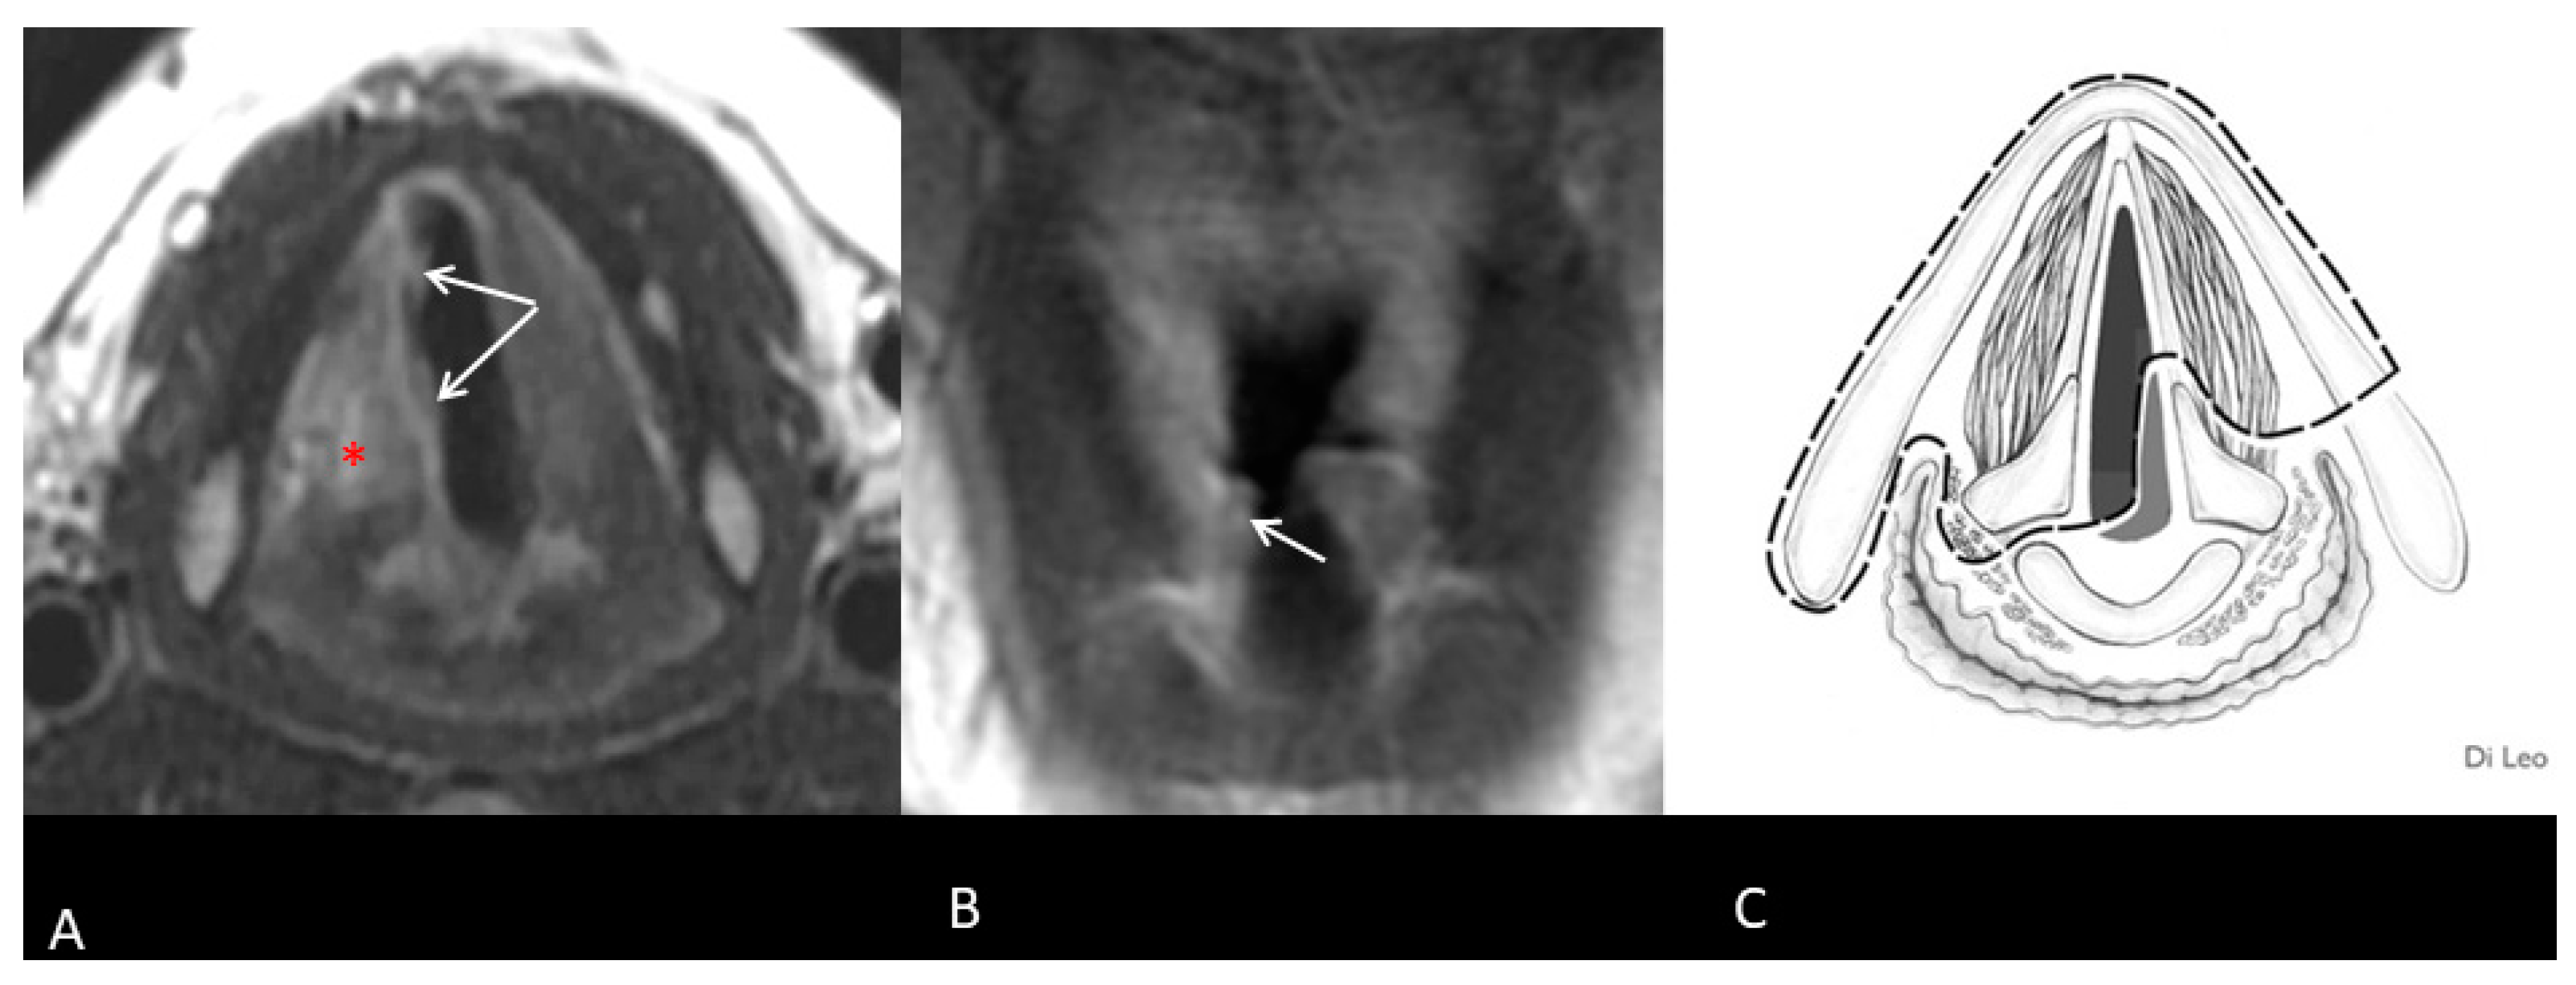

Before salvage surgery, all patients underwent an in-office examination, biopsy, and imaging of the neck and maxillofacial region, with either MRI or CT scans (Figure 1 and Figure 2). The institutional tumor board then reviewed each patient’s case.

Figure 1. Recurrent right glottic SCC after TOLM: MR sequences FSE T2-weighted on the axial plane (A) and FSE T1-weighted after contrast injection on the coronal plane (B). An irregular thickening (arrows) of the right side of the glottic level is suspicious for tumor. Oedematous changes are present (asterisk) (A). The lesion does not involve the subglottic region (B). Axial scheme of resection (Type IIa OPHL + right ARY) (C) [10].